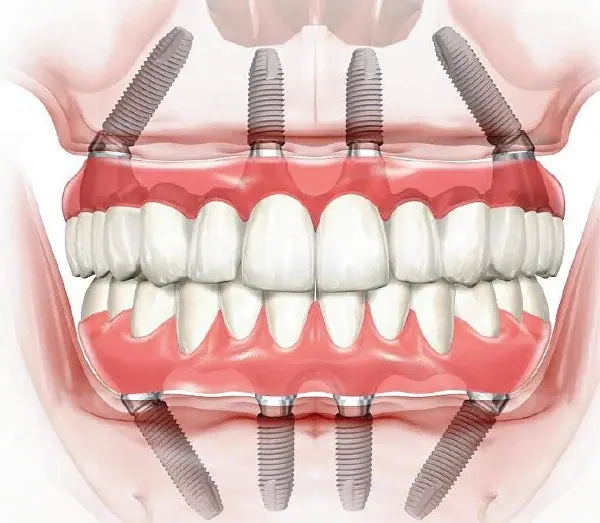

Установка четырёх имплантов

Это ключевой этап операции. Два импланта ставятся вертикально в переднем отделе челюсти, ещё два — под углом до 30° в боковых отделах.

All-on-4 имплантация

Такое расположение обеспечивает максимальную устойчивость конструкции, равномерное распределение нагрузки и прочную фиксацию, достаточную для того, чтобы сразу закрепить временный протез.